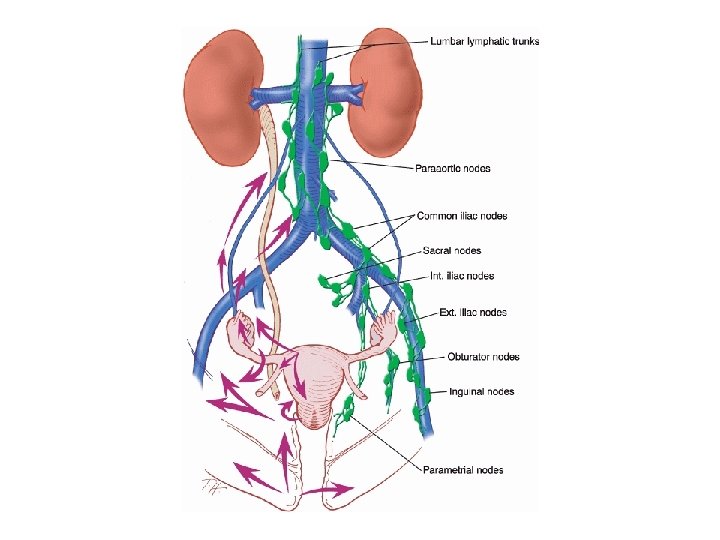

Lymph Drainage • The external genitalia, anus, and anal canal drain to the superficial inguinal nodes • The lower one third of the vagina drains to the sacral nodes and the internal and common iliac nodes • The cervix drains to the external or internal iliac and sacral nodes

Lymph Drainage • The lower uterus drains to the external iliac nodes • The upper uterus drains into the ovarian lymphatics to the lumbar nodes. The lymphatics of the ovaries drain out of the pelvis to the lumbar nodes

Lymph Drainage • Cervical Cancer: – Drains 1 st to the parametrial nodes --> obturator nodes --> pelvic nodes --> para-aortic • Uterine Cancer: – Drains 1 st to the pelvic nodes or para-aortic. • Ovarian Cancer: – Can metastasize to either the pelvic or para-aortic nodes.